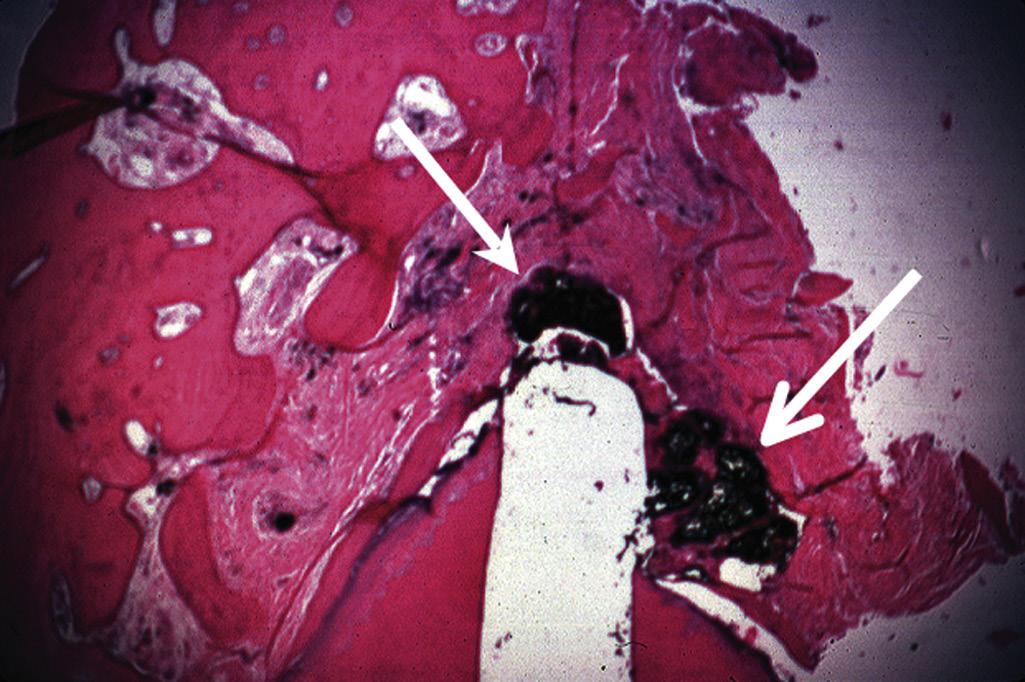

Pulpal and periapical pathoses do not develop without the presence of bacterial contamination.15,16 Kakehashi and collaborators created pulp exposures in conventional and germ-free rats.15 In the germ-free rats, minimal inflammation only occurred throughout the 72-day observation period. Further, pulpal tissue in these animals was not devitalized but rather showed calcific bridge formation by day 14, with normal tissue apical to the dentin bridge (Fig. 1.7, A). In contrast, infection, pulpal necrosis, and abscess formation occurred by the eighth day in conventional rats (Fig. 1.7, B). The bacteriological investigation by Sundqvist examining the flora of human necrotic pulps supports the findings of Kakehashi and collaborators15 and Möller and coworkers.16 Sundqvist examined previously traumatized intact teeth with necrotic pulps, with and without apical pathosis. The root canals of teeth without apical lesions were aseptic, whereas those with periapical pathosis had positive bacterial cultures.17

• Fig. 1.7 A, No inflammation is seen in an exposed pulp (P) of a germ-free rat. Food particles and other debris (D) are packed into the chamber. B, Periapical lesion is apparent in a conventional rat after pulp exposure. (Courtesy Dr. H. Stanley.)